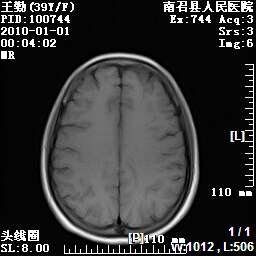

以下是引用随光逐影在2010-1-22 9:03:00的发言:[br]考虑左侧中颅窝(蝶骨翼区)脑膜瘤侵犯蝶骨翼并突入左侧眼眶。

以下是引用水过无痕在2010-1-22 14:55:00的发言:[br]一、定位:颅外占位;二、定性:恶性可能性大;三、组织来源:来源于左侧眼外直肌或其他部位;考虑为:横纹肌肉瘤>转移瘤>脑膜瘤.